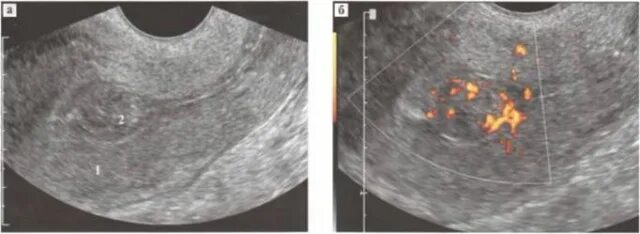

Эндометрий 9 мм